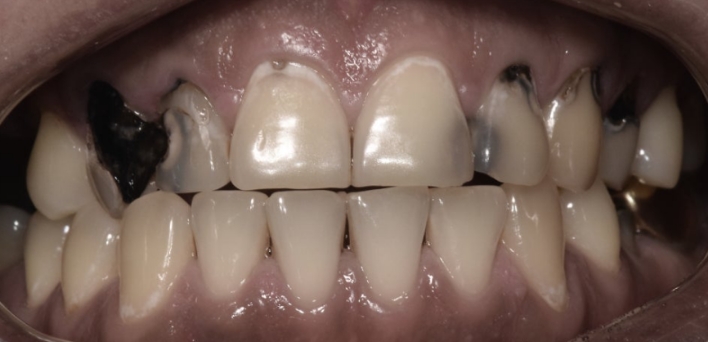

우리 얼굴에서 미소는 첫인상을 좌우합니다. 이런 좋은 인상을 위해 라미네이트를 고려 중이시라면,

많은 것들을 고려해야 합니다. 라미네이트 시 무조건 하얗고, 얇기만 한 치아가 좋은 것은 아닙니다.

개개인의 얼굴마다 비율에 맞게 이상적인 치아의 형태가 있습니다.

더서울치과의원은 정확한 안모 분석을 통한 프로파일 예측 치료로 심미성은 물론 치아 본연의 기능 회복까지 가능하도록

안면 근육과 기능, 치아 형태, 비율, 크기, 교합, 색감 등 전반적인 비율을 맞추어 본인에게 잘 맞는 치아의 형태로 복원합니다.

※ 더서울치과의원은 의료법을 준수하며 위 케이스는 실제 환자의 동의를 얻은 사례로 치료 전, 후가 동일한 환경에서 촬영되었습니다.

환자 케이스에 따라 부작용이 발생할 수 있습니다. 이 부분은 의료진의 충분한 상담과 체크를 통해 예방하고 줄일 수 있습니다.

[심미치료 부작용] 시술 후 치아 시림, 보철물 파손 등의 부작용이 발생할 수 있어 개인별 치아 상태에 따른 정확한 진단과 사후 관리가 중요합니다.